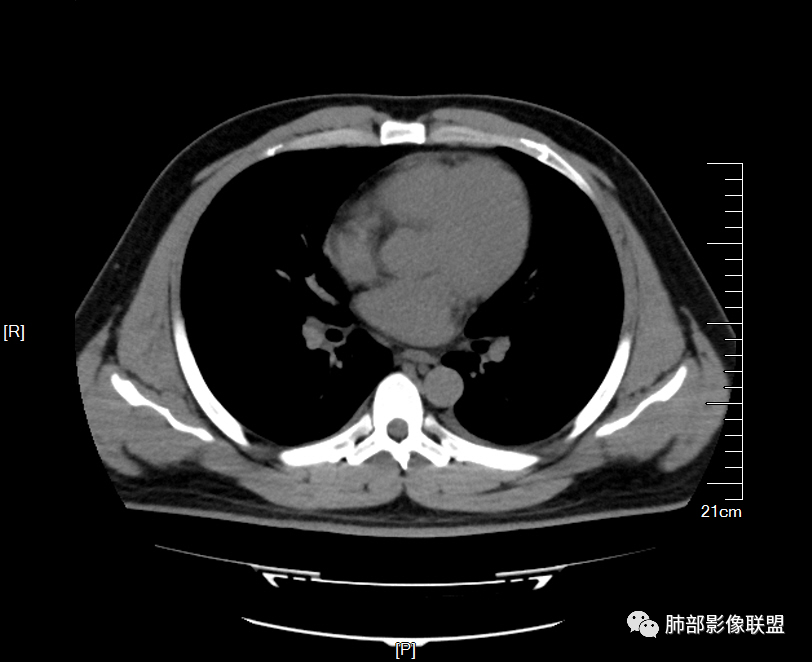

【每日晨读】 双肺满布磨玻璃结节,原来如此!

男32岁。既往曾发现血肌酐升高.此次因左足痛6天入院。有痛风、高血压病史。两肺弥漫性的病变,小片状或者结节状为主病变,小叶中心分部为主,边界不清。心影比较饱满,肝实质密度均匀的降低。考虑为肝损害的影像学改变。综合考虑多功能脏器的损害,肺部损害肺泡炎?肺水肿?或病毒性的肺炎?

年轻男性,痛风史,高血压史,肌酐高,左足痛6天入院。胸CT:双肺多发弥漫性磨玻璃结节影,大小不一,部分融合,上中下肺都有,中内带多,胸膜下少。部分血管束略增粗,小叶内间隔、小叶间隔增厚,下肺明显,左室大。叶裂胸膜增厚。临床有痛风,左足痛6天,考虑:心衰、间质性肺水肿?弥漫性肺泡出血?鉴别:MPA,肺肾综合征,痛风结节等。

痛风入院。无肺部症状

少量积液,脂肪肝